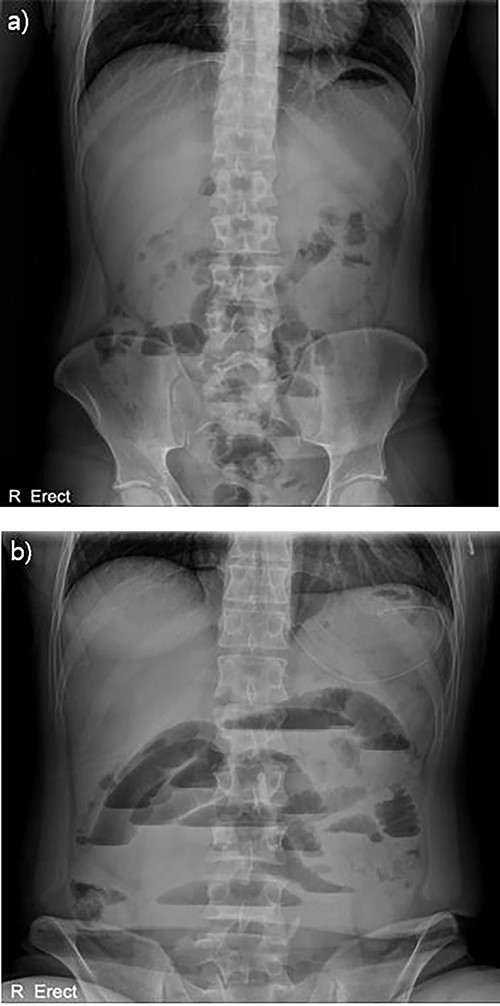

Abdominal X-ray findings (a) initial findings before admission; (b) 12-h follow-up findings revealing step ladder sign.

With no indications for immediate surgical intervention, the initial treatment plan for the patient was decided for conservative management with non per os (NPO) and Levin tube drainage. The patient, however, complained of aggravated abdominal pain after 12 h of conservative care, with elevated WBC count of 15 590/mm3. Changes were found in the abdominal X-ray showing manifestations of newly appeared step-ladder sign (Fig. 1a and b), and the CT scan displayed aggravated dilation of small bowel with a leading point of the mechanical obstruction in the LLQ area (Fig. 2).